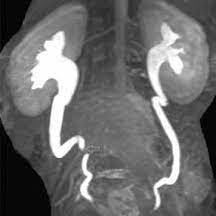

Resonancia nuclear magnetica de vias urinarias. Urorresonancia. EN. Codigo 883435 (2022)